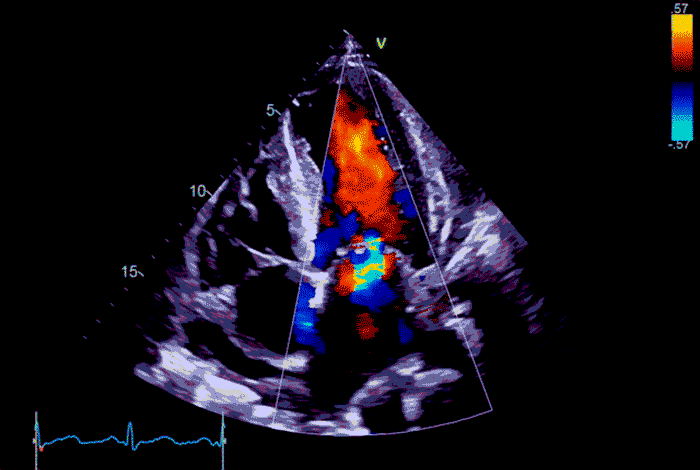

Допплер-эхокардиография

Допплерография — это принцип, основанный на эффекте Доплера: ультразвук меняет частоту, когда отражается от движущихся частиц (в частности, эритроцитов).

Поэтому допплеровский метод, в отличие от стандартного УЗИ, отражает не анатомию, а гемодинамику сердца.

Соответственно, допплер-эхоКГ показывает направление и скорость кровотока, а также градиенты давления крови. Исследование назначают, чтобы выявить регургитацию, шунты и признаки перегрузки камер.

Допплеровский режим встроен во все современные УЗ-аппараты. Он сочетается со стандартным B-режимом — серым 2D-изображением, которое отражает анатомию органа. Технически допплерография может выполняться трансторакально, через пищевод или в рамках стресс-эхоКГ. То есть с поверхностным или чреспищеводным датчиком — как с нагрузкой, так без неё.

цветной показывает направление и турбулентность потока крови;